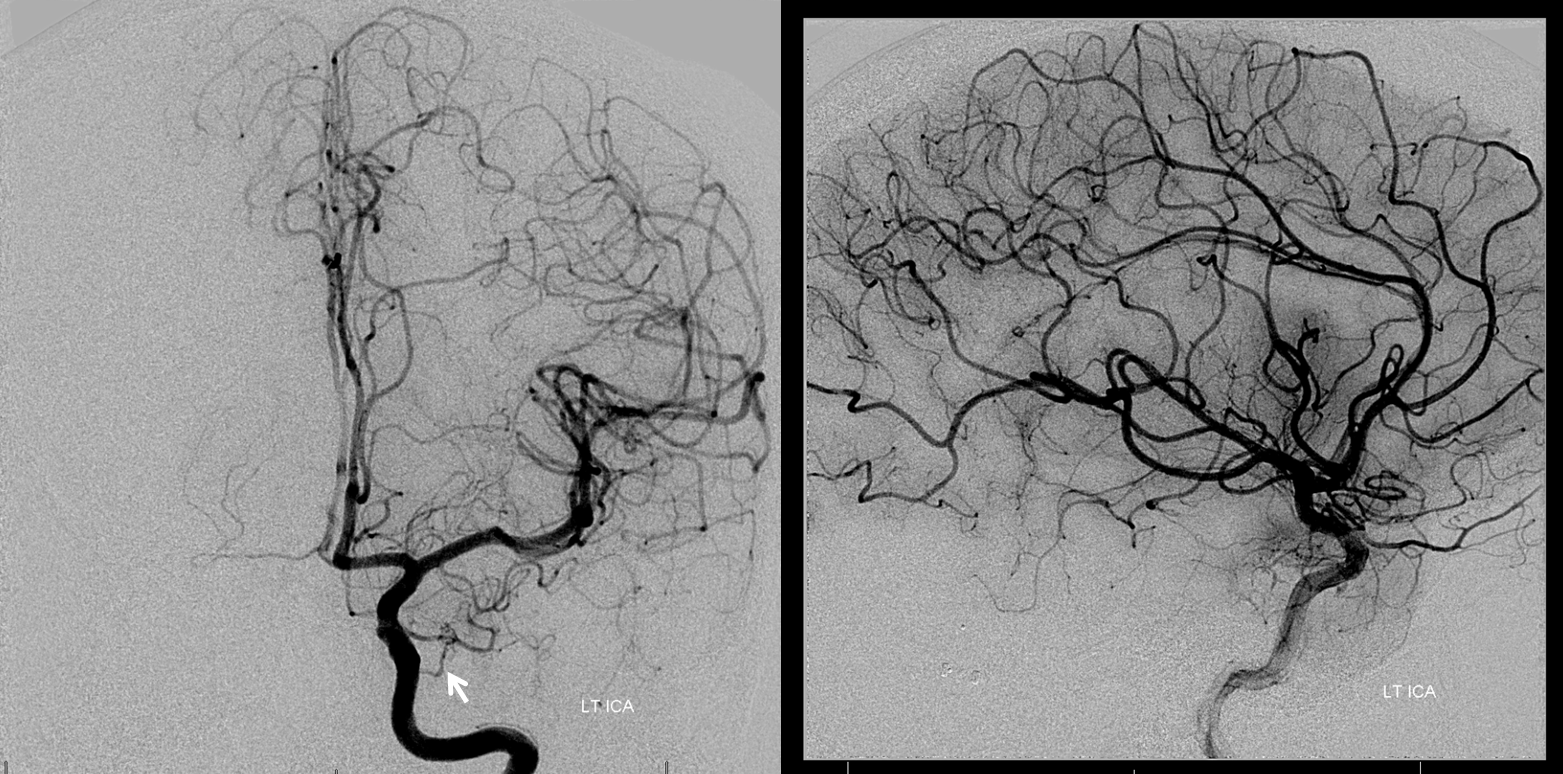

Хирургические процессы при эмболизации гемангиомы на фото